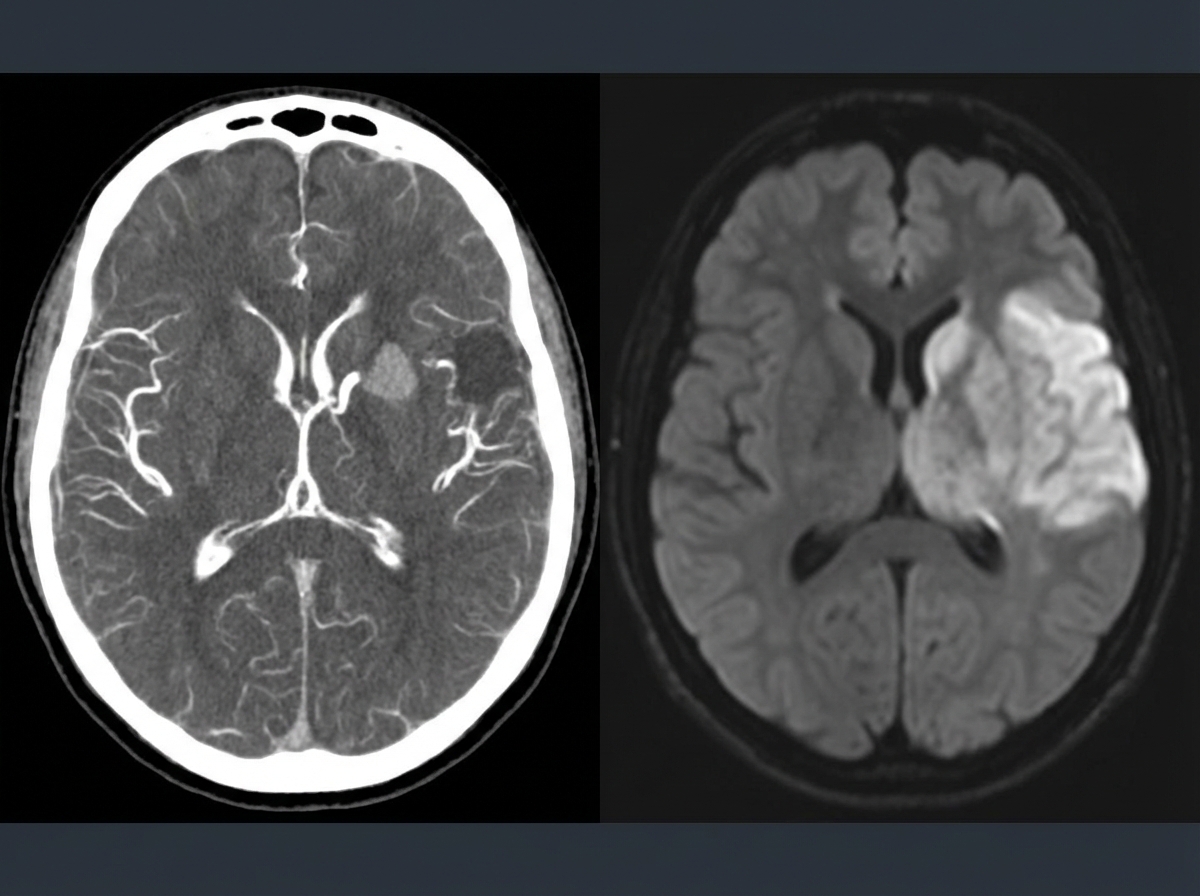

- Initial Workup: Non-contrast head CT (rule out hemorrhage), EKG, basic labs.

- Imaging: MRI (DWI) + MRA head/neck within 24h.

- TIA is a transient neurologic deficit without infarction; rule out stroke with a non-contrast head CT.